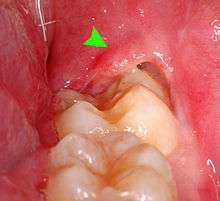

Gutta-percha point indicating abscess origin